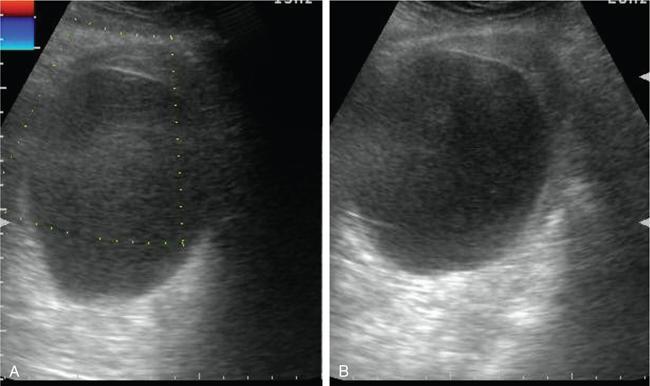

Fig. 11.16.1.3 Adnexal torsion without mass lesion: (A) Axial and (B) coronal T2W1 in an 18-year-old with intermittent episodes of severe lower abdominal pain shows an enlarged left ovary located in the midline in the pouch of Douglas (arrows). Multiple small follicles are seen displaced to the periphery (arrowheads). (C) There is extensive haemorrhage within the ovarian stroma as confirmed with blooming on GRE (asterisks). (A and B) Note the thickened pedicle including the fallopian tube (curved arrows). Oophorectomy was performed for the gangrenous ovary.

Fig. 11.16.1.4 Adnexal torsion without mass lesion: (A) Grey-scale USG in an adolescent girl with symptoms of acute pelvic pain, nausea and vomiting shows an enlarged right ovary (arrowheads) with heterogeneous stoma and multiple small follicle. (B and C) Colour flow imaging shows arterial flow within the pedicle (curved arrows), but absent intraovarian vascularity. (D) Sagittal, (E) coronal, (F) axial T2WI and (G) GRE confirms the enlarged right ovary with haemorrhagic stroma and small follicles, situated within the pouch of Douglas in the midline (short thick arrows). Note the thickened right pedicle including the fallopian tube (long thin black arrows). Detorsion with oophoropexy was performed.